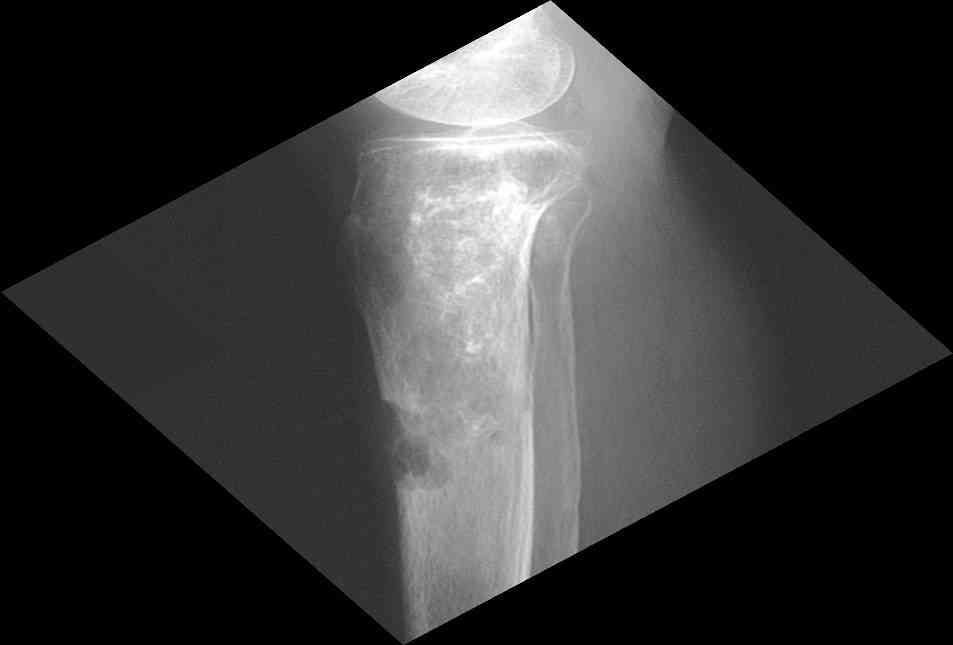

Представленные Вами данные о пациенте 57 дет с болезнью Альбертс-Шенберга чрезвычайно интересны, но диагноз вызывает большие сомнения. Для мраморной болезни характерно прееобладание склероза, а на представленных рентгенограммах преобладает симметричная дезорганизация архитектоники губчатой кости в эпиметафизарной зоне дистальных отделов бедер и голеней.

Мне кажется, представленные рентгенограммы скорее соответствуют варианту фиброзной дисплазии который был описан М. Campanacci (1976) или

обызвествляющей фиброме H.E.Schlitter (1958).

Уважаемый Константин Иванович! Полностью согласен с проф. Михайловым, данный случай не похож на мраморную болезнь, при которой имеется резкое, строго симметричное и генерализованное уплотнение костной ткани (остеопетроз), и кость оказывается построенной преимущественно из гомогенного компактного костного вещества. Для примера привожу случай из архива нашего института (бедренные, плечевые кости и таз, рис 1,2,3)

Изменения структуры костей у Вашего пациента больше похожи на полиоссальную форму фиброзной дисплазии или болезнь Педжета, возможены также инфаркты костного мозга б.берцовых костей. К сожалению, качество снимка не очень хорошее, непонятно, сохранен ли кортикальный слой б.берцовых костей по передней поверхности.

Для примера привожу случай из архива американской ассоциации рентгенологов (ACR) - развитие злокачественной фиброзной гистиоцитомы на левой б.берцовой кости у пациента с множественными инфарктами костного мозга (рис 4,5 - левая, рис 6 - правая)